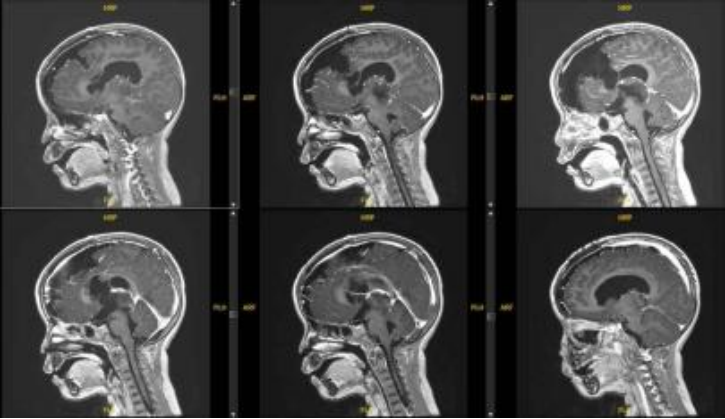

患者女,4岁6月,症状为双上肢震颤、右侧踝阵挛。院外头颅MRI平扫示松果体区占位性病变并梗阻性积水、间质性脑水肿。在上海儿童医学中心张江院区神经外科进一步行头颅MRI平扫+增强检查,于松果体区见团块样占位,大小约29.4*26.7*26.5mm,T1WI低信号,T2WI稍高信号,有明显不均匀强化。影像学诊断为右侧丘脑至松果体区占位,考虑恶性肿瘤。

患儿术前MRI图像